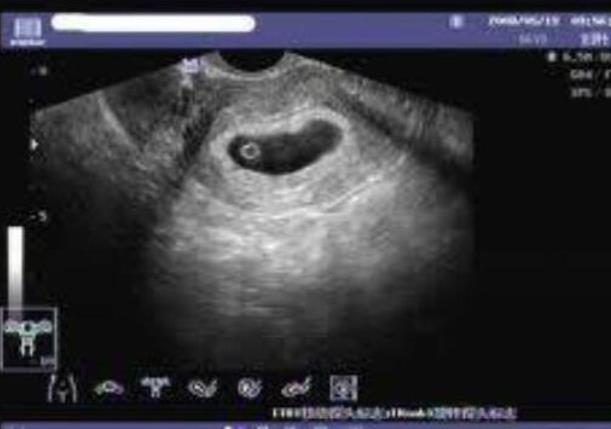

子宮內(nèi)膜

我們要知道的就是,大連生殖中心試管嬰兒之所以能夠有著較高成功率,就是因?yàn)樗麄冊诟鱾€方面都善于把控子宮里面,其實(shí)對于試管嬰兒成功率來說也是有很大的影響,子宮里面會成為影響妊娠率的重要條件,好的子宮內(nèi)膜在胚胎植入之前能夠提供良好的條件,不好的子宮內(nèi)膜同樣就像是一個貧瘠的土壤一樣,所以說優(yōu)良的種子也很難在這其中進(jìn)行生長,那么子宮內(nèi)膜的機(jī)械損傷以及子宮肌瘤,還有子宮腺肌癥,可以不同程度地影響我們吸煙或者是體重指數(shù)過高,精神因素也會影響成功率。